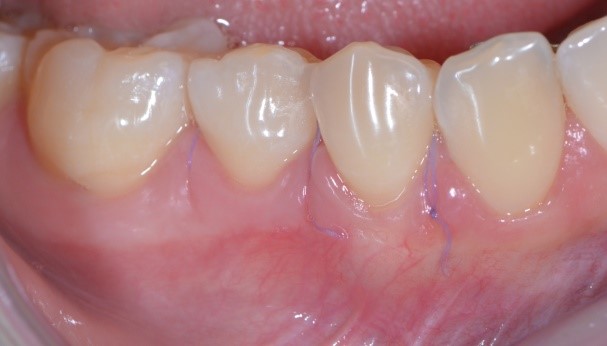

Perché, secondo te, Francesca ha accettato di farsi tagliuzzare in 2 punti per risolvere questo problema? Te lo spiego io: perché io sapevo di poterle dare questa guarigione a 10 giorni

e questa a sei mesi.

Questa consapevolezza mi ha permesso di proporle la cosa nel modo giusto e lei non ha avuto dubbi nell’accettarla. E anche se qualcuno nel mondo parodontale critica la chirurgia mucogengivale, sono convinto che abbia fatto benissimo ad accettarla!